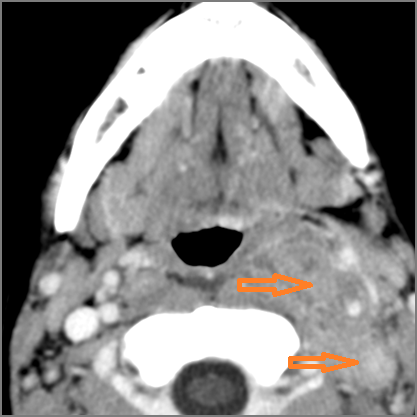

There is excessive enhancement or thickening of the fat or other soft tissues within or surrounding the buccal space, masticator space, floor of the mouth, submandibular space or the adjacent superficial fascia or subcutaneous fat and skin. [Yes/No]

There is edema or abscess within the fat of the adjacent parapharyngeal and retropharyngeal space. [Yes/No]

There is edema or abscess within the adjacent parapharyngeal and retropharyngeal spaces. [Yes/No]